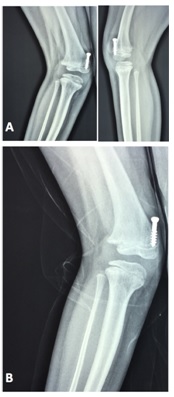

Figura 3: Colocación correcta del tornillo para hemiepifisiodesis en un paciente portador de valgo de tobillo.

Figura 4: Paciente 3, portador de una dismetría congénita. Goniometría que ilustra la dismetría y una incurvación a nivel de la tibia derecha (A). Disposición correcta de los tornillos en el frente y perfil a nivel de la rodilla izquierda (B).

Sólo en un paciente (paciente 11) se utilizó esta técnica a nivel de la fisis tibial distal medial para la corrección de un valgo de tobillo a izquierda, observándose un mal resultado dado el aumento de la deformidad de 2 grados, evidenciado por el ángulo tibioastragalino, con 2 años y 1 mes de seguimiento y con 11 años y 1 mes de edad cronológica al momento del último control, por lo cual ya se está planificando una nueva cirugía para la corrección de la deformidad. Esta mala evolución podría estar relacionada con la técnica de colocación del tornillo, el cual fue colocado de lateral a medial y de proximal a distal, con el objetivo de evitar molestias a nivel del maléolo interno, observándose como el tornillo deja de atravesar la fisis a medida que progresa el crecimiento (Figura 5).

Figura 5: Técnica incorrecta (ver texto). Paciente 11, portador de un valgo de tobillo a izquierda, operado a los 9 años de edad cronológica (A). Muestra una mala evolución con el tornillo fuera de la fisis y con un aumento del valgo de unos 2 grados (B) a los 11 años y 1 mes de edad cronológica.